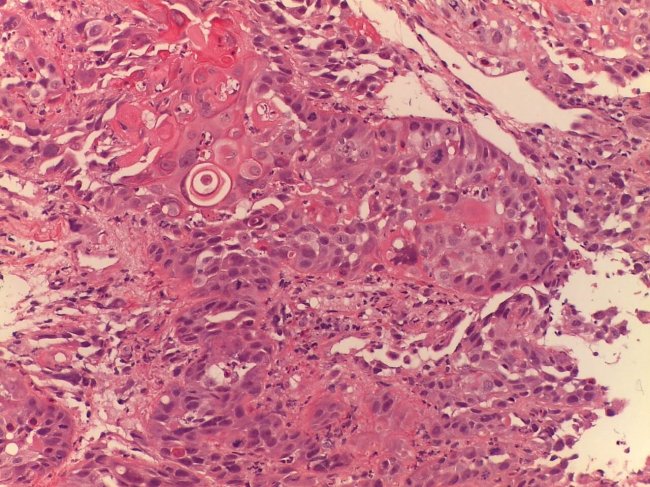

Consiste num procedimento realizado para diagnosticar patologia pulmonar, através da colheita de tecido do pulmão que é examinado ao microscópio.

Histopatologia

Imunohistoquímica

Estudos de marcadores moleculares e genéticos